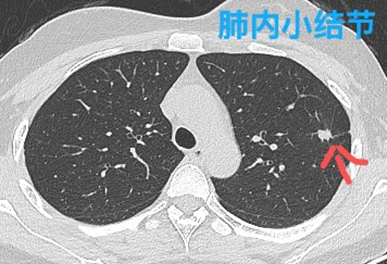

(2)肿块:指直径≥30mm的占位性病灶。

(3)结节:指直径<30mm的占位性病灶。